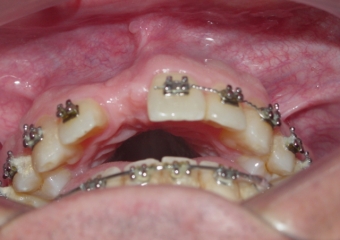

Imagem após enxerto ósseo